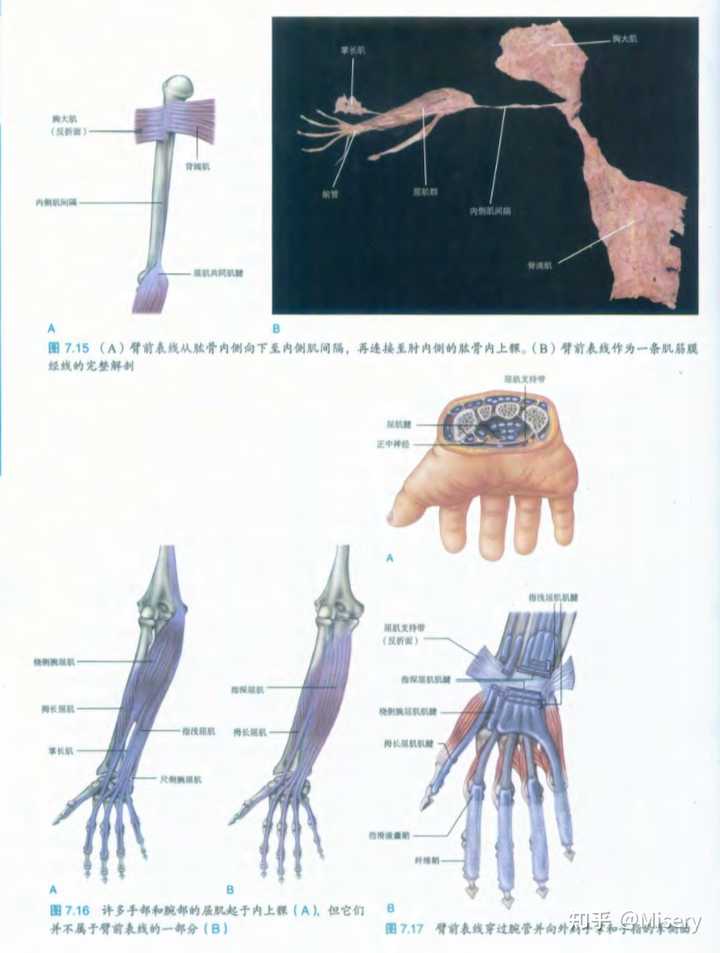

一个激活的是臂前表链,一个激活的是臂前深链 |

前深链大鱼际激活同时胸小肌用力,更容易胸式呼吸 |

当中指用力前表链激活,引发背阔肌用力,腹式呼吸启动。 |